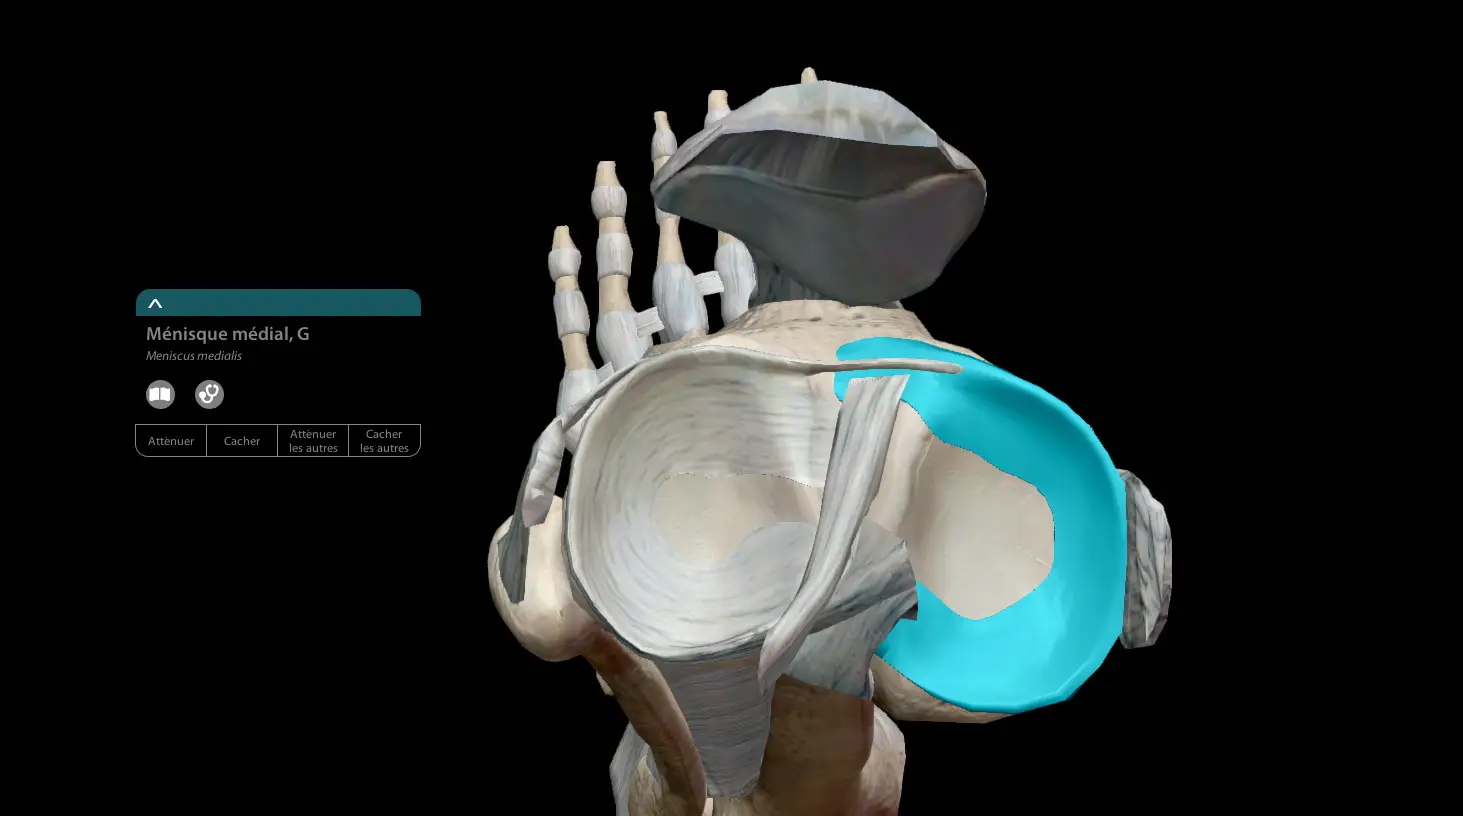

Comme nous l'avions évoqué lors de la présentation de la rupture du ligament croisé, le genou est une articulation complexe composée de diverses structures (os, ligaments, muscles, liquide synovial...) Parmi celles-ci, on retrouve les ménisques. Au nombre de deux, ils recouvrent la partie supérieure du tibia.

Le fémur étant "arrondi", et le tibia "plat", les ménisques sont présents au milieu dans le but de combler l'espace. Leur rôle permet d'amortir les chocs, car l'articulation du genou est globalement très sollicitée. Ils ont aussi un rôle de stabilisateur, parce qu'ils empêchent le genou de sortir de son axe. Il est possible de vivre sans ménisques, mais le processus de gonarthrose sera accéléré.

On retrouve deux ménisques situés de part et d'autre de la rotule :

- Le ménisque interne ou médial situé à proximité de l'autre jambe

- Le ménisque externe ou latéral, regardant vers l'extérieur.

Leur rôle est essentiel dans la stabilisation du genou avec les ligaments croisés. Leur large structure permet de mieux répartir les pressions exercées sur le genou. Lors de mouvements de course et de pivot, le poids exercé sur notre articulation est très important, surtout lorsque l'on se retrouve sur un appui unipodal. Leur structure élastique va faciliter le mouvement de flexion et extension du genou.